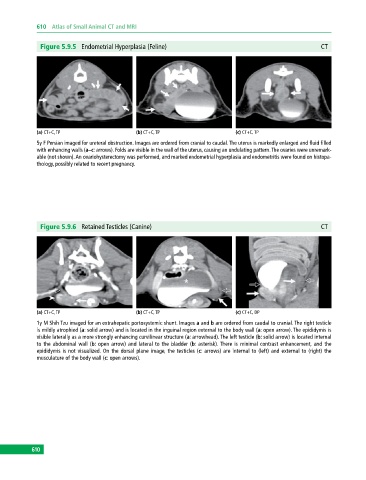

Figure 5.9.5 Endometrial Hyperplasia (Feline) CT

(a) CT+C, TP (b) CT+C, TP (c) CT+C, TP

5y F Persian imaged for ureteral obstruction. Images are ordered from cranial to caudal. The uterus is markedly enlarged and fluid filled

with enhancing walls (a–c: arrows). Folds are visible in the wall of the uterus, causing an undulating pattern. The ovaries were unremark

able (not shown). An ovariohysterectomy was performed, and marked endometrial hyperplasia and endometritis were found on histopa

thology, possibly related to recent pregnancy.

Figure 5.9.6 Retained Testicles (Canine) CT

(a) CT+C, TP (b) CT+C, TP (c) CT+C, DP

1y M Shih Tzu imaged for an extrahepatic portosystemic shunt. Images a and b are ordered from caudal to cranial. The right testicle

is mildly atrophied (a: solid arrow) and is located in the inguinal region external to the body wall (a: open arrow). The epididymis is

visible laterally as a more strongly enhancing curvilinear structure (a: arrowhead). The left testicle (b: solid arrow) is located internal

to the abdominal wall (b: open arrow) and lateral to the bladder (b: asterisk). There is minimal contrast enhancement, and the

epididymis is not visualized. On the dorsal plane image, the testicles (c: arrows) are internal to (left) and external to (right) the

musculature of the body wall (c: open arrows).